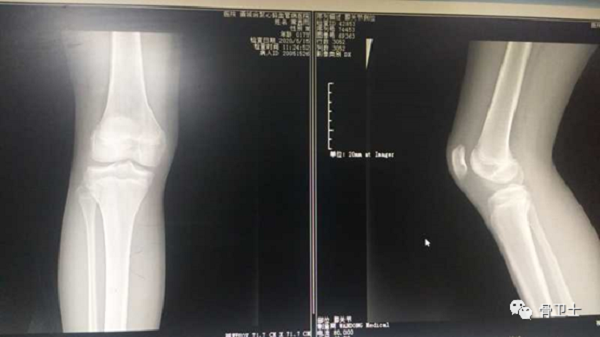

辅助检查:右膝关节核磁检查显示,右膝髌股关节不稳(高位髌骨、股骨滑车发育不良,髌骨向外侧稍移位),右膝髌上囊大量积液。

4.png

5.png

初步诊断:右膝关节髌骨半脱位